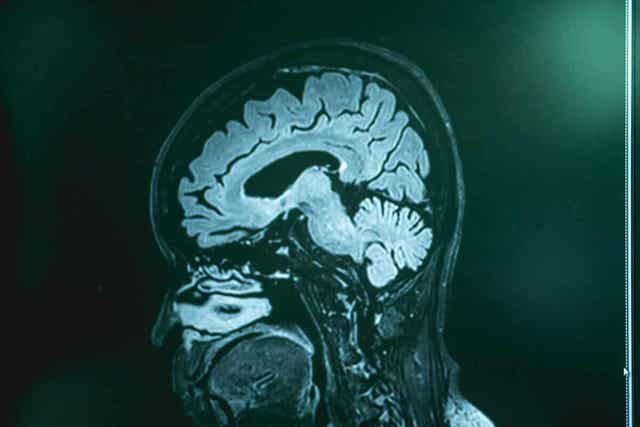

Kuten MSD-käsikirjoissa todetaan, tämä sairaus voidaan vahvistaa vain lannepunktiolla (ja sitä seuranneella aivo-selkäydinnesteanalyysillä) sekä aivobiopsialla. Lääkärit suorittavat testejä ihmisille, joilla on naegleriaasin oireita ja jotka ovat olleet kosketuksissa käsittelemättömän makean veden kanssa edellisinä päivinä.

Toisaalta kuvantamistutkimukset (tietokonetomografia ja magneettikuvaus) eivät tunnista sairautta, mutta voivat sulkea pois muut mahdolliset terveysongelmat. Kun aivo-selkäydinneste on saatu, lääkärit suorittavat viljelmiä tai geneettisiä analyyseja ameeban genomin etsimiseksi.